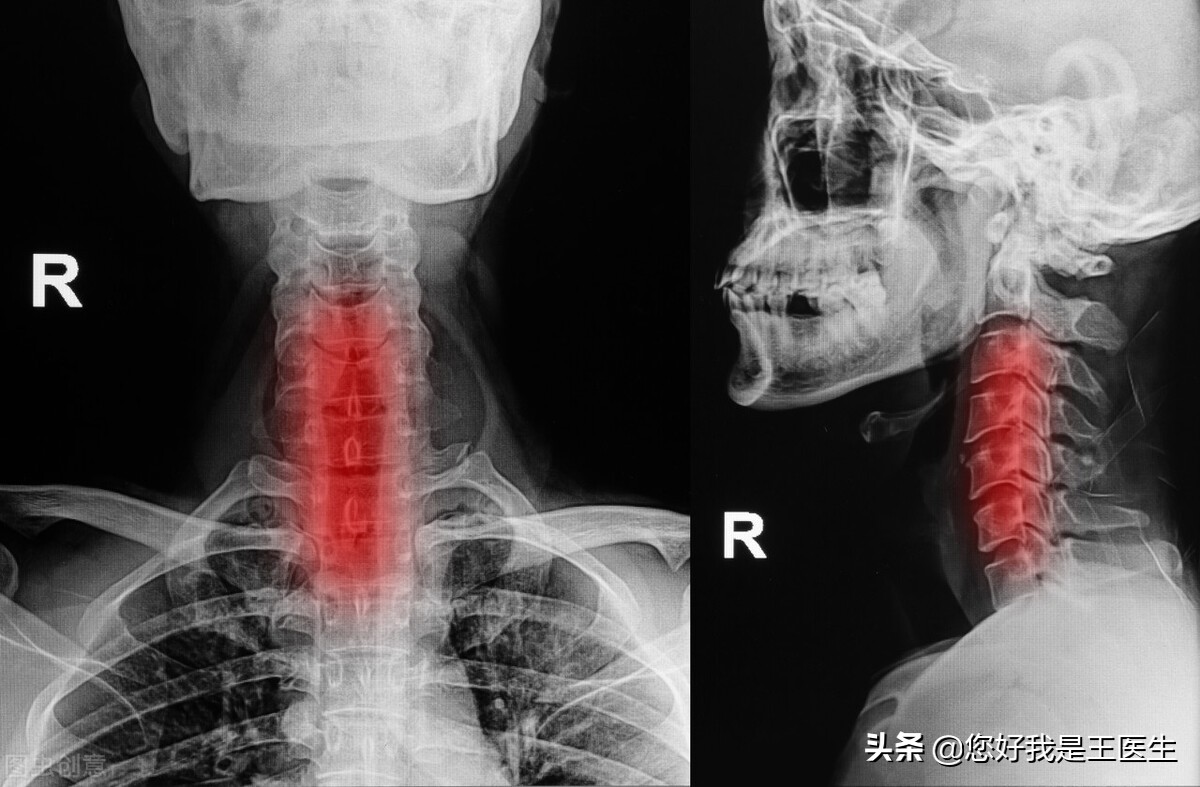

1.一方面呢,颈椎病的朋友大部分都是伏案工作者,长此以往,整个颈部都是向前倾的,与我们正常的生理曲度是相反的。

2.颈椎病的患者,也有一部分经常睡高枕头,或者呢,有的时候靠在沙发背儿上就睡着了。时间一长也会导致生理曲度的改变,从而出现眩晕,头疼等症状。

但是,这样的情况,去掉枕头是改变不了什么的。因为当我们去掉枕头睡觉的话,我们头部的枕骨变成了支点,颈椎还是处于一个伸直的状态,又怎么能保证正常的生理曲度呢?